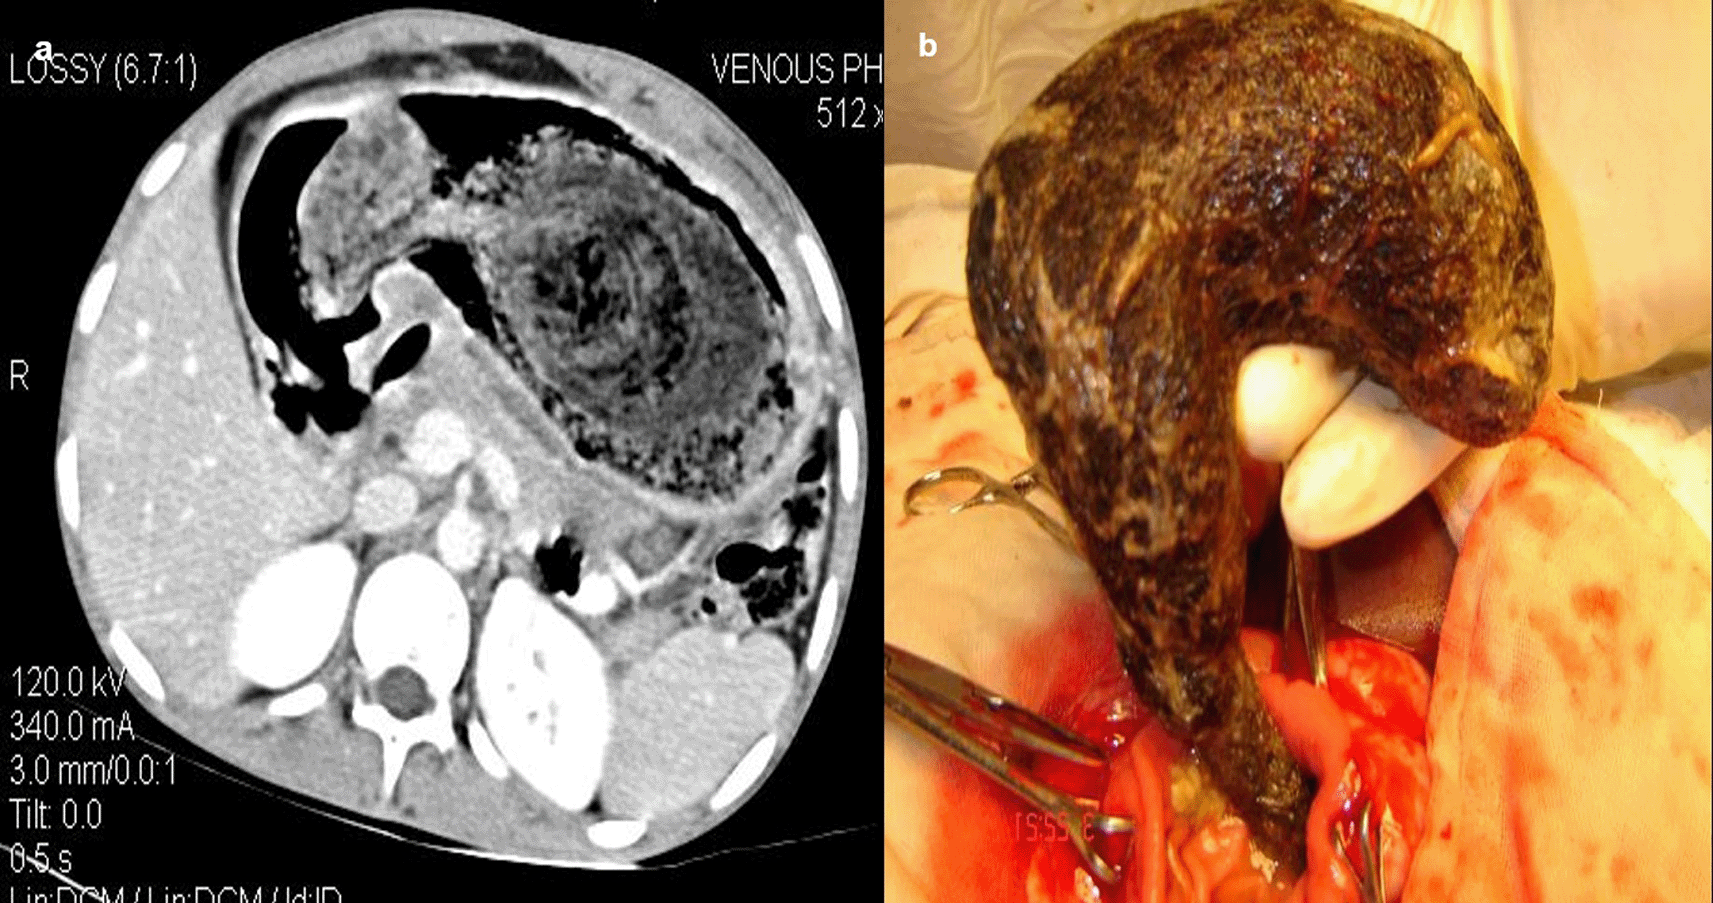

Case 4: An 18-year-old woman patient came with a history of abdominal pain and vomiting on and off for 15 days. Contrast enhanced computed tomography (CECT) reveals a heterogeneous lamellated non-enhancing soft tissue density mass (with a wide attenuation range from -70 to 70 HU) intraluminally in the stomach, conforming to its shape and extending into the antrum, pylorus, and minimally into the duodenal cap suggestive of trichobezoar. Gastrotomy revealed the ball of hair in the stomach.

When a patient cannot provide a sufficient history or has swallowed things that are not naturally radio-opaque, the diagnosis of an ingested foreign body is frequently missed. If a foreign body is suspected and is not visible on a Radiograph because of its radiolucent nature, a CT scan of the abdomen or chest may be beneficial8 (Figure 4a,b).

Gastrotomy revealed the ball of hair in the stomach (b).